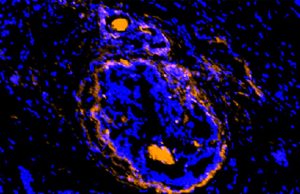

Cancerous tumors, surrounding cells illuminated by new imaging agent

Scientists at Washington University School of Medicine in St. Louis have developed a new imaging agent that could let doctors identify not only multiple...